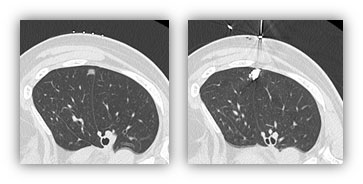

近年、検診CTの普及で早期肺がんが多く発見されるようになりました。図に肺がんの胸部CTを示しますが、淡い影(すりガラス)と濃い白い部分(中心部分)が混在しています。中心部分の割合が多いほど悪性度が高いことがわかっています。肺がんで重要なのはリンパ節転移の有無です。一般に、リンパ節転移がないのであれば、他の臓器に転移の可能性は非常に低くなります。このようながんを画像的非浸潤がんと命名しています。これまでの研究から、中心部分の割合が全体の25%までと定義されています。図では左の2つのCTまでが画像的非浸潤がんにあたります。画像的非浸潤がんの条件を満たした肺癌に対しては、基本的に部分切除を適応させています(中枢病変は例外)。当科ではさらに、リピオドールマーキングを併用した肺部分切除を行っています。